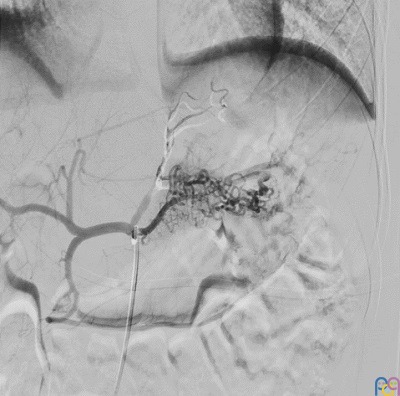

En el episodio actual, acudió a Urgencias por un episodio de hematemesis, melenas y síncope que precisó en dos ocasiones la administración de suero salino fisiológico 0,9% a 20 ml/kg e ingreso en UCIP para vigilancia. Presentó una anemización progresiva hasta hemoglobina de 6,9 g/dl, precisando transfusión de dos concentrados de hematíes. Durante su ingreso se realizó ecografía abdominal y gastroscopia sin alteraciones significativas y valoración por Otorrinolaringología descartando foco del sangrado a dicho nivel. Al tercer día de ingreso, se realizó angiografía mostrando una malformación vascular de tipo arterial en región fúndico-cardial en aspecto de “ovillo”.

Ante dichos hallazgos se decidió traslado a nuestro centro, donde se realizó una arteriografía diagnóstico-terapéutica. La embolización de la malformación transcurrió sin incidencias (Fig. 1 y Fig. 2).